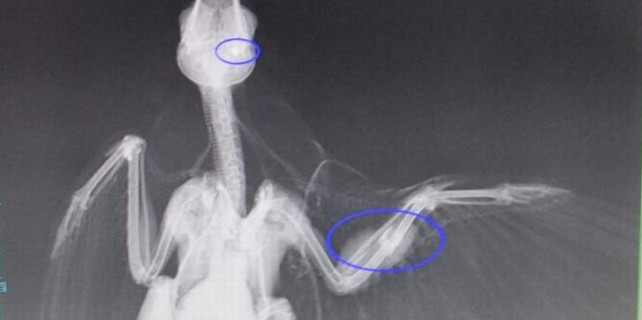

Bursa’da kanadından ve gagasından saçma mermisi ile yaralanan Karam adlı erkek karga cerrahi operasyonla tekrar hayata döndürüldü. Nilüfer ilçesinde avcıların tüfeğinden çıkan saçma ile yaralanan ve hastane çalışanlarının Karam adı verdiği erkek karga Nilüfer Belediyesi Veteriner İşleri Müdürlüğü’nde yapılan cerrahi müdahalenin ardından hayata döndürüldü. Vatandaşlar tarafından bulunan ve Nilüfer Belediyesi Veteriner İşleri Müdürlüğü ekipleri tarafından kliniğe getirilen Karam için hemen ameliyathane hazırlandı. Kanadından ve gagasından yaralanan karga, yaklaşık yarım saatlik bir operasyonun ardından yoğun bakım ünitesine alındı. Operasyonu yapan Veteriner Doktor Ayşe Yazıcı, “Bu yaralı karga duyarlı bir vatandaşımızın bize ulaşması sonucu ekiplerimiz tarafından buraya getirildi. Karganın durumunu görünce hemen ameliyathaneyi hazırladık. Çünkü kanadında ve gagasında saçma mermileri vardı. Sanırım avcılar tarafından atılmış. Yaklaşık yarım saat süren bir operasyon sonrasında hayata dündü. Şu anda yoğun bakım ünitesinde dinleniyor. Sağlığına kavuştuğu zaman doğal ortamına geri salınacak” dedi.